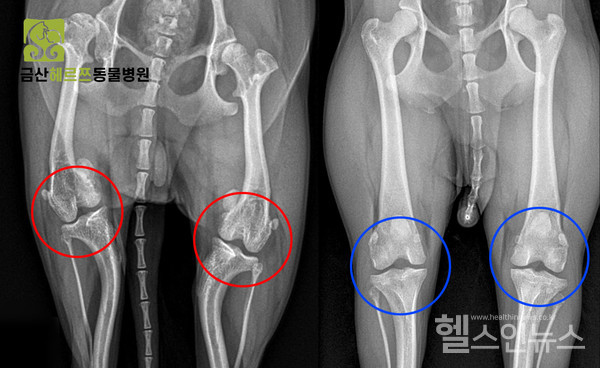

슬개골탈구는 슬개골 이탈 범위나 정도에 따라 1기~4기로 나뉜다. 1기는 외부 요인으로 탈구되지만 금방 정상 위치로 돌아오고 2기는 인위적인 힘을 가해야만 복구가 된다. 슬개골탈구 1기, 2기의 경우 탈구 범위가 좁고 통증이 심하지 않기 때문에 약물 치료를 우선 진행한다. 3기, 4기는 슬개골이 계속 빠져있는 상태이며 4기의 경우 인위적인 힘을 가해도 원상태로 복구가 불가하다. 슬개골탈구는 진행성 질환이기 때문에 한 번 진행되기 시작하면 되돌릴 수 없다. 따라서 슬개골탈구 2.5기부터는 외과적 수술을 통해 치료하는 것을 권한다.

슬개골탈구수술은 탈구의 정도, 다리 변형 상태, 십자인대 파열 여부 등에 따라 수술 방법이 달라진다. 보통 슬개골이 빠지지 않게 고정해 주고 슬개골을 포함한 대퇴사두근의 축을 일(一)자로 맞춰 주는 방법을 사용한다. 슬개골탈구수술은 수술 후 관리도 매우 중요하다. 산책은 30분 미만으로 과하지 않게 해 주는 것이 좋고 앞서 말한 두 발로 서는 직립 보행, 높은 곳에서의 점프 등은 자제하는 것이 좋다.